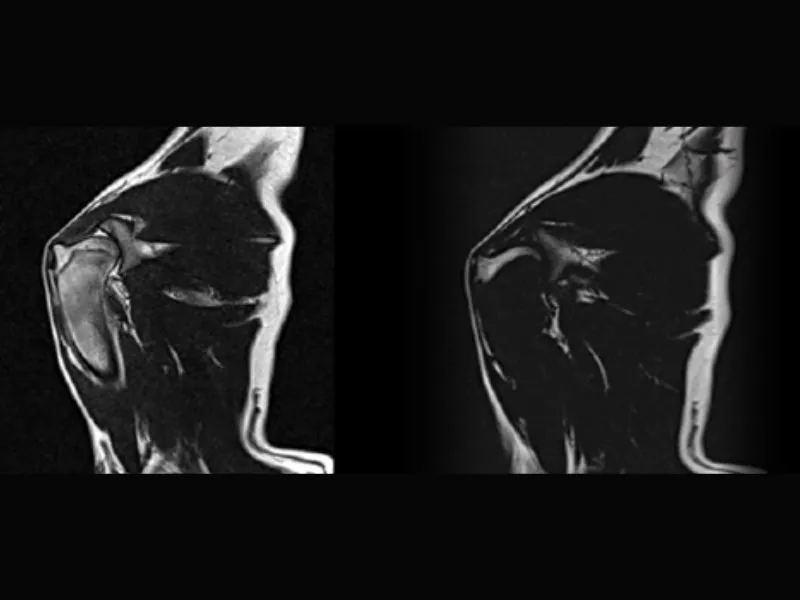

Clinical images

Small animals